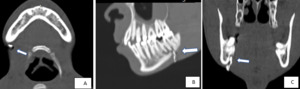

To further evaluate the condition, a multidetector computed tomography (MDCT) scan was performed using the following parameters: 110 kV, 120 mAs, 16 × 0.7 mm collimation, with image acquisition at a 3 mm slice thickness and secondary reconstruction at 1.5 mm. The patient then underwent an axial MDCT scan with post-processing multiplanar reconstructions in the axial, sagittal, and coronal planes.

The scan revealed a focal cutaneous opening without any evidence of a localized abscess or soft tissue mass (figure 2A). However, an osteolytic lesion was identified in the periapical region of the right mandibular second molar, accompanied by cortical thinning and a focal bony defect (Figure 2B, 2C).

As demonstrated in our case, iso-volumetric, high-resolution datasets obtained during contrast-enhanced CT scanning—combined with post-processed multiplanar reconstructions (axial, sagittal, and coronal) and advanced imaging techniques such as volume rendering (Figures 2–4) and maximum intensity projection—enable comprehensive mapping of the sinus tract. This approach allows for accurate identification of the tract’s type, length, internal origin, and any associated complications, such as bone erosion or abscess formation.14,15